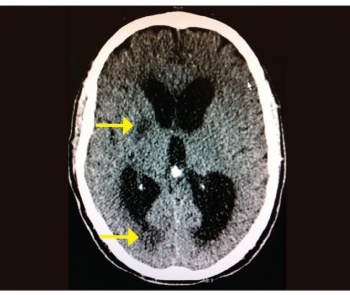

He was mechanically ventilated and remained in the intensive care unit (ICU) for the following 14 days. Investigations showed neutrophil leucocytosis and raised inflammatory markers in his blood. Meningoencephalitis was the working diagnosis from the beginning and he was covered with antimicrobial and antiviral from day one. His CSF analysis showed 35 WBC per/ul (95% lymphocytes), glucose of 3.5mmol (plasma 7.6mmol) and protein of 0.74g/L. Extensive microbiological analysis (including polymerase chain reaction [PCR]) failed to identify any organisms. The repeat CT brain three days later showed areas of low densities at right internal capsule and right temporo-parietal lobe, which are new since the first scan (see Figure 2) and which were suggestive of infarcts, and stroke was a possibility at that stage and was discussed with his family. The course of management, however, remained the same (completed full course of parenteral antibacterial and antiviral) and these areas totally disappeared in the later scans with no adequate explanation to their nature and implication.